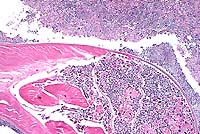

Case 5-1. Colon. Shows subserosal, colonic adenocarcinoma with cyst and abscess formation. 4X

Spontaneous carcinomas of the small and large intestine are reported to be rare in rats. References disagree regarding the most common site of origin, and the most common site may differ in different strains and stocks. In this Long-Evans rat, there was transmural invasion of the neoplasm through the colonic wall with subserosal abscess formation, but metastases were not observed.

AFIP Diagnosis: Colon: Adenocarcinoma, colonic, Long-Evans rat, rodent.

Conference Note: There was considerable variation in the slides distributed for this case. Several slides viewed in conference demonstrated minimal or no invasion of neoplastic cells into the tunica muscularis, and no neoplastic cells were present in the subserosal abscess. This led some participants to a diagnosis of atypical hyperplasia or carcinoma in situ. However, in other slides, invasive growth indicative of malignancy is evident.